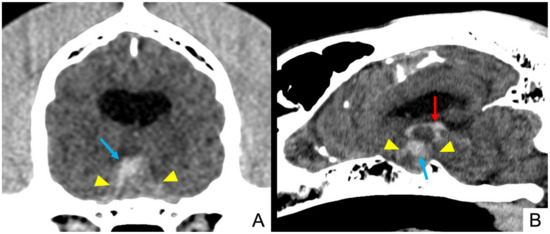

3.4. Imaging Findings

| Signalment | Pre-Contrast Heterogeneity | Pre-Contrast Hyperattenuation | Hyperattenuating Foci | Contrast Enhancement | Post-Contrast Hypovascular Areas | CT Diagnosis |

|---|---|---|---|---|---|---|

| 1. Mixed breed MN, 9.75 y, 24.6 Kg | Yes | Yes | Yes | Heterogeneous | Yes | Pituitary mass with intralesional haemorrhage |

| 3. Mixed breed FN, 12.7 y, 4.7 Kg | Yes | Yes | Yes | Heterogeneous | Yes | Pituitary mass with intralesional haemorrhage |

| 4. Italian Bracco dog F, 12.8 y, 27 Kg | Yes | Yes | Yes | Heterogeneous | Yes | Pituitary mass with intralesional haemorrhage |

| 5. Mixed breed FN, 12.7 y, 30 Kg | Yes | Yes | Yes | Heterogeneous | Yes | Pituitary mass with intralesional haemorrhage |

| 6. Beagle FN, 7.6 y, 16.6 Kg | Yes | Yes | Yes | Heterogeneous | Yes | Pituitary mass with intralesional haemorrhage |

| 7. Labrador Retriever F, 5 y, 31.2 Kg | Yes | Yes | Yes | Heterogeneous | No | Pituitary mass with intralesional haemorrhage |

| 8. Labrador Retriever FN, 10.8 y, 35 Kg | Yes | Yes | Yes | Heterogeneous | Yes | Pituitary mass with intralesional haemorrhage |

| 9. Mixed breed FN, 5.8 y, 21 Kg | Yes | Yes | Yes | Heterogeneous | Yes | Pituitary mass with intralesional haemorrhage |

| 10. Labrador Retriever FN, 8.6 y, 29 Kg | Yes | Yes | Yes | Heterogeneous | Yes | Pituitary mass with intralesional haemorrhage |

| 11. Boxer FN, 11.4 y, 27.4 Kg | Yes | Yes | No | Heterogeneous | No | Pituitary mass with intralesional haemorrhage |

| 12. Springer Spaniel M, 13.7 y, 18.7 Kg | Yes | Yes | No | Heterogeneous | Yes | Pituitary mass with intralesional haemorrhage |

| 13. Mixed breed M, 11.1 y, 33 Kg | Yes | Yes | No | Heterogeneous | Yes | Pituitary mass with intralesional haemorrhage |

| 14. Mixed breed M, 9.8 y, 14.5 Kg | Yes | Yes | No | Heterogeneous | Yes | Pituitary mass with intralesional haemorrhage |

| 15. Corso dog FN, 9.4 y, 43 Kg | Yes | Yes | Yes | Heterogeneous | No | Pituitary mass with intralesional haemorrhage |

| 16. English Bulldog M, 6.1 y, 28 Kg | Yes | Yes | No | Heterogeneous | Yes | Pituitary mass with intralesional haemorrhage and necrosis |

| 17. Mixed breed M, 9.3 y, 9.3 Kg | Yes | Yes | Yes | Heterogeneous | Yes | Pituitary mass with intralesional haemorrhage and necrosis |

| 18. Mixed breed M, 3.2 y, 15 Kg | Yes | Yes | Yes | Heterogeneous | Yes | Pituitary mass with intralesional haemorrhage and necrosis |

| 19. Mixed breed M, 11.1 y, 27.6 Kg | Yes | Yes | No | Heterogeneous | Yes | Pituitary mass with intralesional haemorrhage |